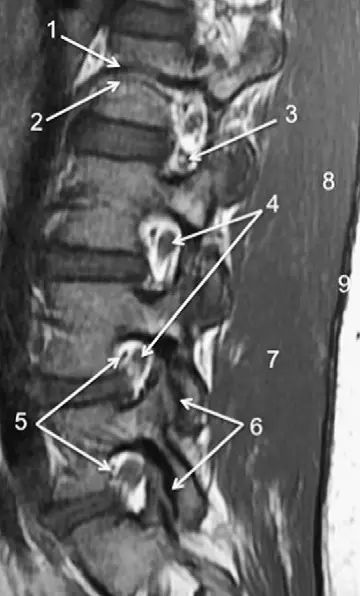

脊柱的MRI解剖